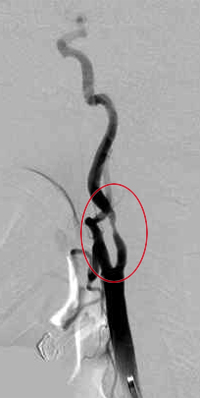

血栓内膜剥離術の手術前

血栓内膜剥離術の手術後